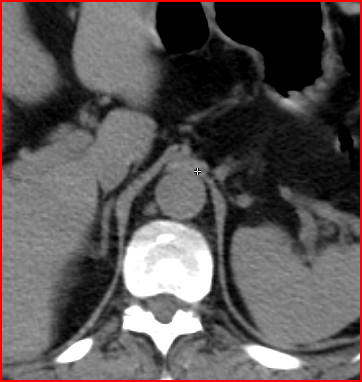

5. Multiplex bone metastases. Bone scintigraphy, anterior (a) and posterior (b) whole body scans. SPECT-CT sagittal plane, fusion image (c) and CT image (d). Obvious bone structural changes cannot be identified on the CT scan yet.

The examination is appropriate for staging a malignant process and following-up bone metastases. It is clinically most suitable for lesions that frequently present bone metastasis, primarily in case of prostate-, breast-, lung cancer and neuroblastoma. It is, however only indicated in cases where the soft tissue involvement of the tumor is big enough to suggest a higher incidence of bone metastasis; before radical surgeries and for the selection of patients who would benefit form a palliative radionuclide therapy. Otherwise, scintigraphy is advisable in case of any primary tumor, if the suspicion for metastasis is raised, e.g.: bone pain, pathologic radiological or lab results (elevated serum ALP and tumor marker levels). Bone metastases in most cases are located in bones that contain red bone marrow (skull, vertebrae, ribs, sternum, pelvic bones and the proximal bone segments of the limb) and usually show a multiplex appearance. Activity increase can be seen typically, metastases that cause activity decrease are rare; they could occur in cases of thyroid gland tumor, renal carcinoma, lymphoma and multiple myeloma. Solitary lesions or a few lesions only, due to the aspecific nature of the examination, cause a differential diagnostic problem in many cases, for example vertebral degenerative processes can mimic metastatic activity. Equivocal lesions usually require further, targeted radiological investigations. A negative X-ray examination does not rule out the possibility of a metastatic lesion, since the isotope scan is more sensitive. Therefore, it is possible that it could already be detecting an existing metastasis, while X-ray is still insensitive and unable to show the lesion. (Figure 5.)

SPECT examination of the spine can help in the precise lesion localization within a single vertebra. It is especially useful, since the different pathologic bone processes occur in different predilection sites of the vertebral bone. Bone metastases are commonly located in the dorsal aspect of the vertebral body. Degenerative processes involve mostly the vertebral edge as in the case of spondylophytes in spondylosis. Finally, spondolyathrosis is usually located at the intervertebral facet joints.